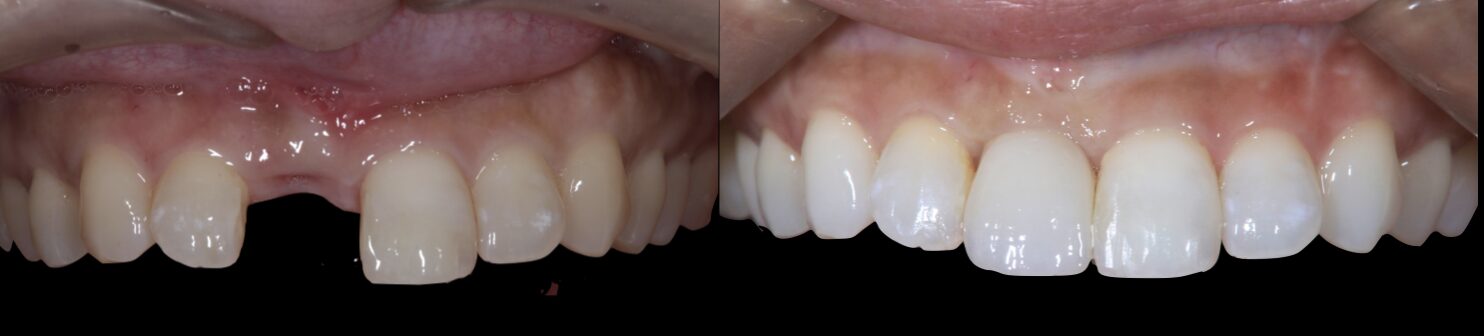

最終補綴物の装着|自然な見た目と噛み心地を回復

治療期間中は仮歯を装着し、歯の形・色・歯ぐきとの調和・噛み合わせを確認しながら調整しました。

最終的に、インプラント上にセラミッククラウンを装着し、前歯としての見た目と機能の回復を図りました。

術前後の比較

今回の症例では、前歯の根が破折し、根の先に膿がたまっていたため、まず感染源を取り除くことが重要でした。

さらに、骨と歯ぐきの一部が失われていたため、感染除去・インプラント埋入・歯ぐきの移植・セラミック補綴を段階的に行いました。

前歯のインプラント治療では、見た目だけでなく、清掃性・噛み合わせ・長期安定性まで考えた治療計画が大切です。